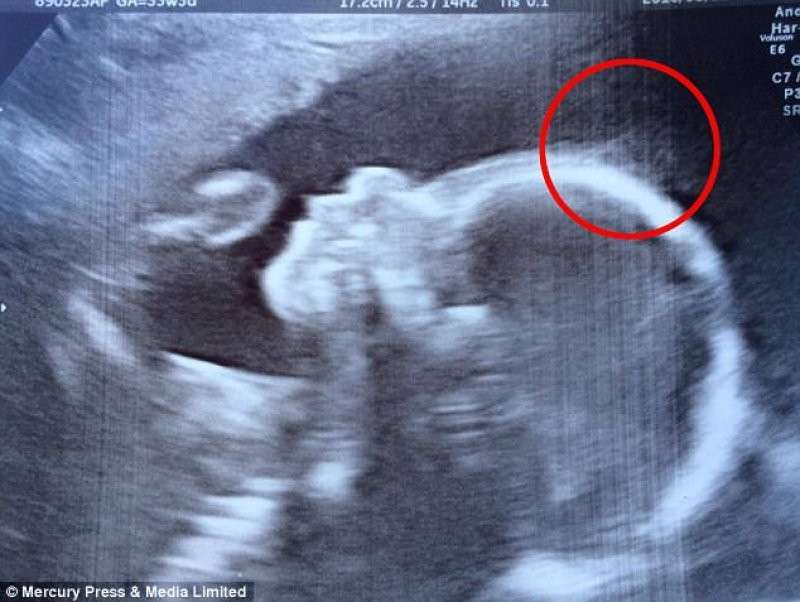

Когда 28-летняя Наташа Гент из Британии на 20 неделе беременности сделала УЗИ, сначала врачи, а потом и она сама увидела на снимке кое-что очень необычное. Посовещавшись, они решили, что это волосы и что, скорее всего, ребеночек родится не лысеньким. Но когда мама увидела свою дочь после родов, реальность превзошла даже самые смелые её ожидания.